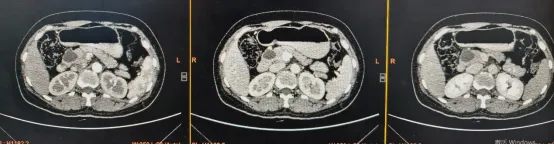

李晓勇教授、陈艳军主任通过影像学技术仔细评估肿瘤范围及位置后,明确表示:可以施行DPPHR术式——切除胰头部肿瘤,同时尽可能保留十二指肠等器官功能完整。

术前,李晓勇教授、陈艳军主任团队通过多学科联合会诊(MDT),结合影像学检查,精准制定手术方案,明确病变边界与血管走行。